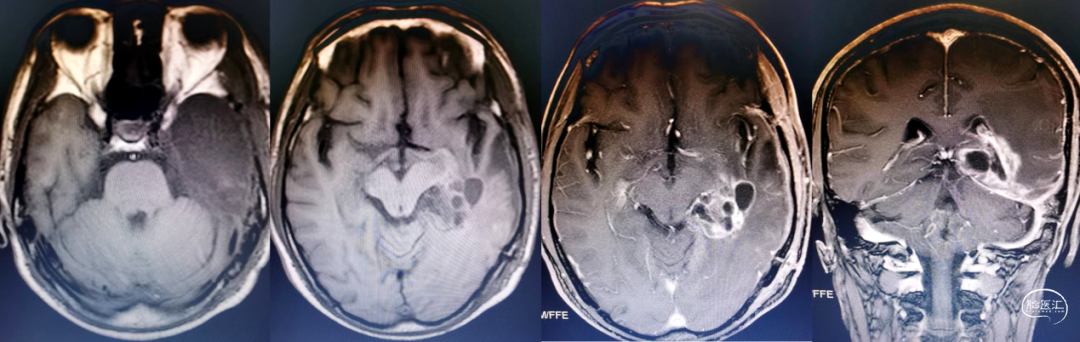

术后病理诊断:右侧丘脑弥漫中线胶质瘤(H3K27突变,WHO 4级)

术后复查:

术后病理诊断:左侧海马复发胶质母细胞瘤(IDH野生型,WHO 4级)